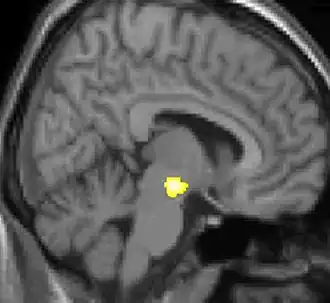

| Diese Kernspintomographie mit eingezeichneter Morphometrie zeigt einen höheren Anteil an Grauer Substanz im Hypothalamus rechts (im Bild links) | ||

Die Positronen-Emissions-Tomographie (PET)-Darstellungen oben zeigen die funktionellen Daten, also die Bereiche, welche bei Schmerzen Aktivität aufweisen, im Vergleich zum Aussehen bei einem schmerzfreien Intervall. Man sieht die sog. Schmerzmatrix, die immer bei Schmerz aktiviert ist und das Areal in der Mitte (in allen drei Ebenen), welches spezifisch im Cluster-Kopfschmerz aktiviert ist. Die VBM Bilder unten zeigen die strukturellen Daten. Hier wird untersucht, ob die Gehirne von Cluster-Kopfschmerz-Patienten anders sind als die Gehirne von Menschen ohne Kopfschmerzen. Nur ein Areal ist anders, da es mehr Graue Substanz enthält: Dieses entspricht dem oben gezeigten funktionellen Areal. Es handelt sich um den Hypothalamus. Dort wird unter anderem der Schlaf-Wach-Rhythmus generiert. Man vermutet daher den Motor des Cluster-Kopfschmerzes im Hypothalamus.[27][28] Mit der 1H-Magnetresonanzspektroskopie konnten auch biochemische Unterschiede zwischen dem Hypothalamus gesunder Menschen und dem Hypothalamus von Cluster-Kopfschmerz-Patienten nachgewiesen werden.[29][30]